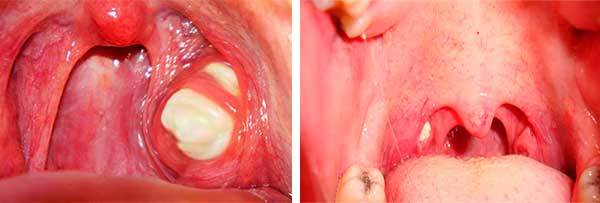

Чтобы ответить на вопрос: почему бывает жёлтое нёбо во рту (смотри фото), следует подробнее изучить предмет внимания.

При осмотре рта помимо языка, дёсен с зубами и внутренних поверхностей щёк видна и вогнутая куполообразная поверхность, ограничивающая ротовую полость сверху.

Это нёбо – покрытая слизистой оболочкой костная конструкция, образованная нёбными отростками двух половин верхней челюсти.

Фибрин после тонзиллэктомии

Тонзиллэктомия – хирургическое удаление воспалившихся гланд. После оперативного вмешательства в ходе первой стадии заживления (до 3-х суток) на местах усекновения образовывается фиброзная плёнка. Она придаёт желтоватый оттенок и может вызвать неприятных запах из ротовой полости человека.

Лечение: горловые полоскания запрещены, потому что могут спровоцировать возобновление кровотечений. Полоскать можно только полость рта, сплёвывая раствор мирамистина или хлоргексина (в соответствии с назначением лечащего врача).

К концу недели после операционного вмешательства желтоватый налёт начинает уменьшаться, а после двух недель полностью исчезает.